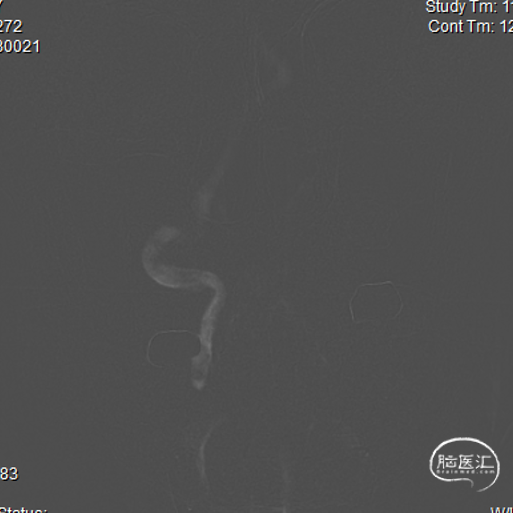

患者平卧位,常规消毒铺巾,局麻下以Seldinger法取右侧股动脉穿刺处,穿刺成功后,置8F股脉鞘。通路建立成功后,进行每公斤体重2/3全身肝素化,用猪尾、单弯导管及高压注射器行脑血管造影术,DSA显示:II型主动脉弓,血管迂曲,双侧锁骨下动脉通畅,右侧椎动脉V1段闭塞,有肌支动脉向V2段注入,V2-V4段可显影,左侧椎动脉V4段纤细,基底动脉及双侧大脑后动脉通畅;双侧颈总动脉及其分支动脉未见明显异常。

因该患者锁骨下动脉成角较大,且直径较为粗大,故采用冠脉6F JR4.0 造影导管,导管改善入路,提供良好支撑,便于微导丝成功通过闭塞段。将JR4.0 造影导管鞘置于右侧锁骨下动脉椎开口处,充分显示椎动脉狭窄部位。

路图指引下,将Pilot150 0.014inch微导丝配合SL-10微导管尝试穿过椎动脉V1段闭塞部位,反复尝试不能通过闭塞段,更换Avigo 0.014inch微导丝,导丝最终成功通过闭塞段,微导管造影证实位于血管真腔,远端血管通常,更换Transend 0.014inch微导丝送至右侧椎动脉V3段,交换出微导管。

沿微导丝送入2.0*20mm 优游球囊于椎动脉狭窄段预扩张,回撤球囊,复查造影提示右侧椎动脉V1段再通,残余长节段狭窄。

沿微导丝先后送入4.0*16mm、4.0*12mm Maurora®药物洗脱支架共2枚于椎动脉狭窄段,定位准确后以分别以12、14atm释放。

复查DSA显示右侧椎动脉残余狭窄大于40%,沿微导丝送入4.5*15mm 优游球囊于椎动脉狭窄段后扩张,回撤球囊。

复查DSA显示右侧椎动脉残余狭窄小于30%,血流通畅,术中无新发部位栓塞;拔出鞘管,股动脉缝合器行血管缝合,止血成功,绷带加压,安返病房,行血压、脉搏监测,常规抗血小板治疗。